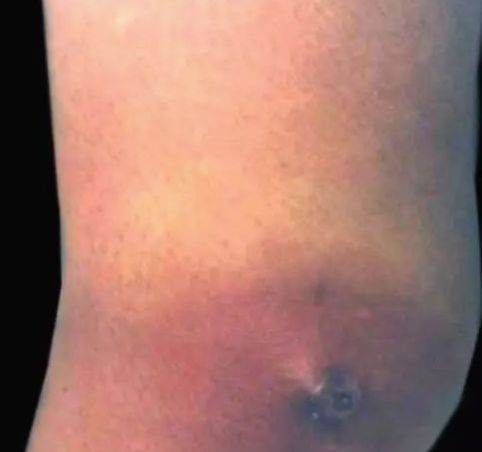

49.下肢蜂窝织炎